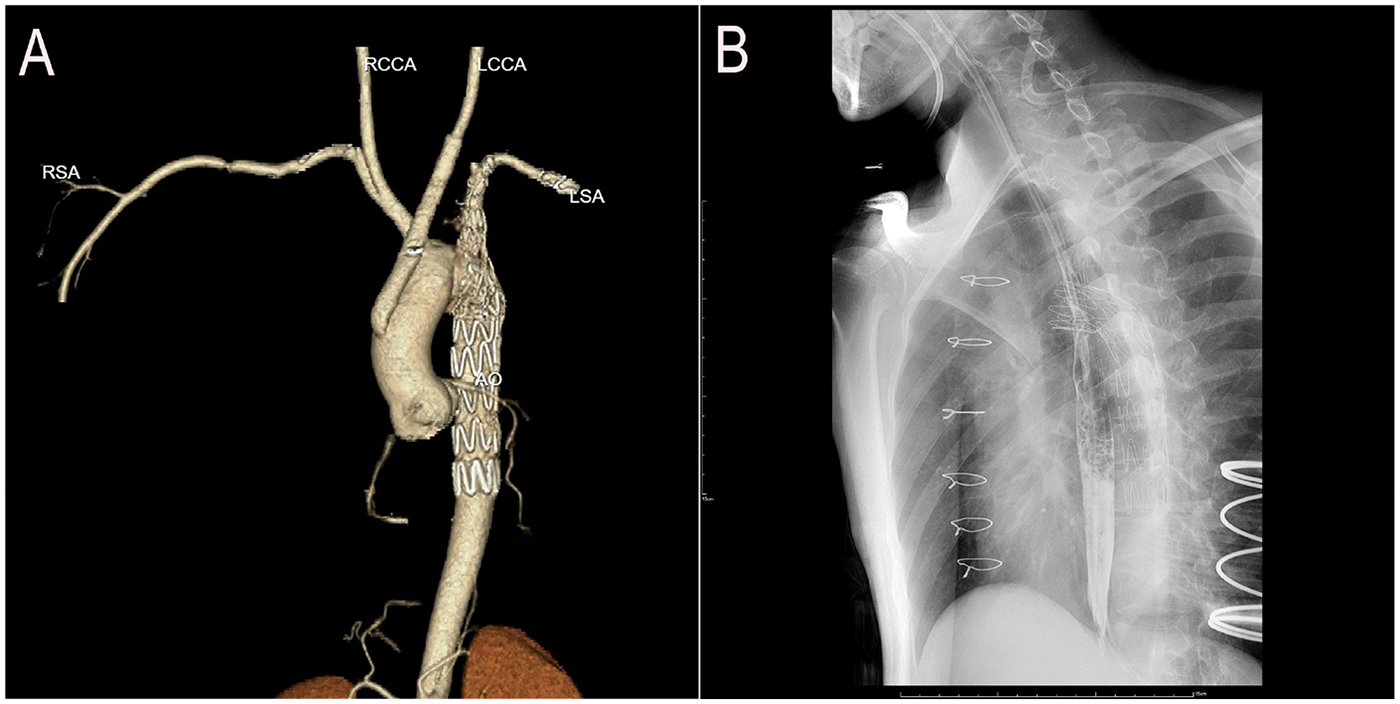

The patient regained consciousness 3 h postoperatively. Esophagoscopy disclosed a 1-cm longitudinal mucosal tear 25 cm from the incisors (Supplementary Video S1), prompting placement of a jejunal feeding tube and gastrointestinal decompression. Mechanical ventilation was discontinued on postoperative day 3. We instituted a regimen of low-volume mediastinal irrigation with normal saline (500 ml every 12 h) combined with low negative pressure drainage, continued for seven days. Following irrigation cessation, the patient was monitored for an additional 48 h. Drainage fluid remained clear and serosanguinous, body temperature normalized, and inflammatory markers (procalcitonin [PCT] and white blood cell count [WBC]) returned to baseline. Bacterial culture of the drainage fluid was negative. Post-cessation computed tomography angiography (CTA) confirmed restored aortic arch anatomy (Figure 3A), allowing removal of the irrigation and drainage systems. Enteral nutrition was maintained for 6 weeks. Subsequent esophagography showed no evidence of esophageal fistula (Figure 3B), enabling gradual dietary advancement. The patient recovered without complications and was discharged (Figure 4). At the three-month postoperative follow-up, he remained asymptomatic but declined follow-up gastroscopy and aortic CTA.

Figure 3

Postoperative imaging follow-up. (A) CTA: Restored aortic arch anatomy after stent graft deployment. (B) Esophagography: Healed esophageal mucosa with smooth contour and no evidence of contrast extravasation or fistula formation.